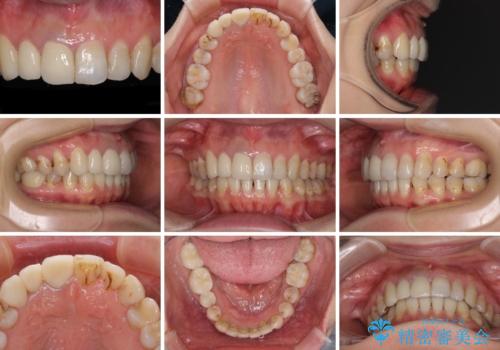

インビザラインによる矯正治療の後に虫歯や銀歯をセラミックにて補綴することとしました。

前歯のむし歯治療の跡や奥歯の目立つ銀歯がなくなり、明るい口元になりました。